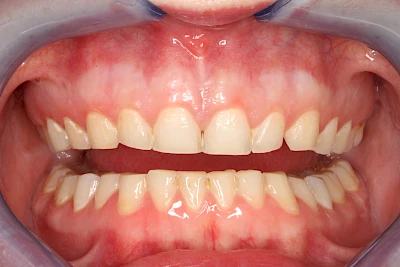

Über die Zeit können verschiedene Prozesse die Zahnhartsubstanzen aufzehren:

- Abnutzung durch Kauen (Abrasion) oder duch durch übermäßiges Knirschen bzw. Pressen (Attrition)

- Säurebedingte Auswaschung (Erosion)

- Knirschen bzw. Pressen und ungünstige Putztechnik (Druck): keilförmige Defekte

Die Zähne können dabei auf Reize (warm, kalt, süß, sauer) oder auch beim Zähneputzen empfindlich oder schmerzhaft sein. In allen diesen Fällen ist es sinnvoll, den Zahnarzt zu kontaktieren und das weitere Vorgehen abzustimmen.